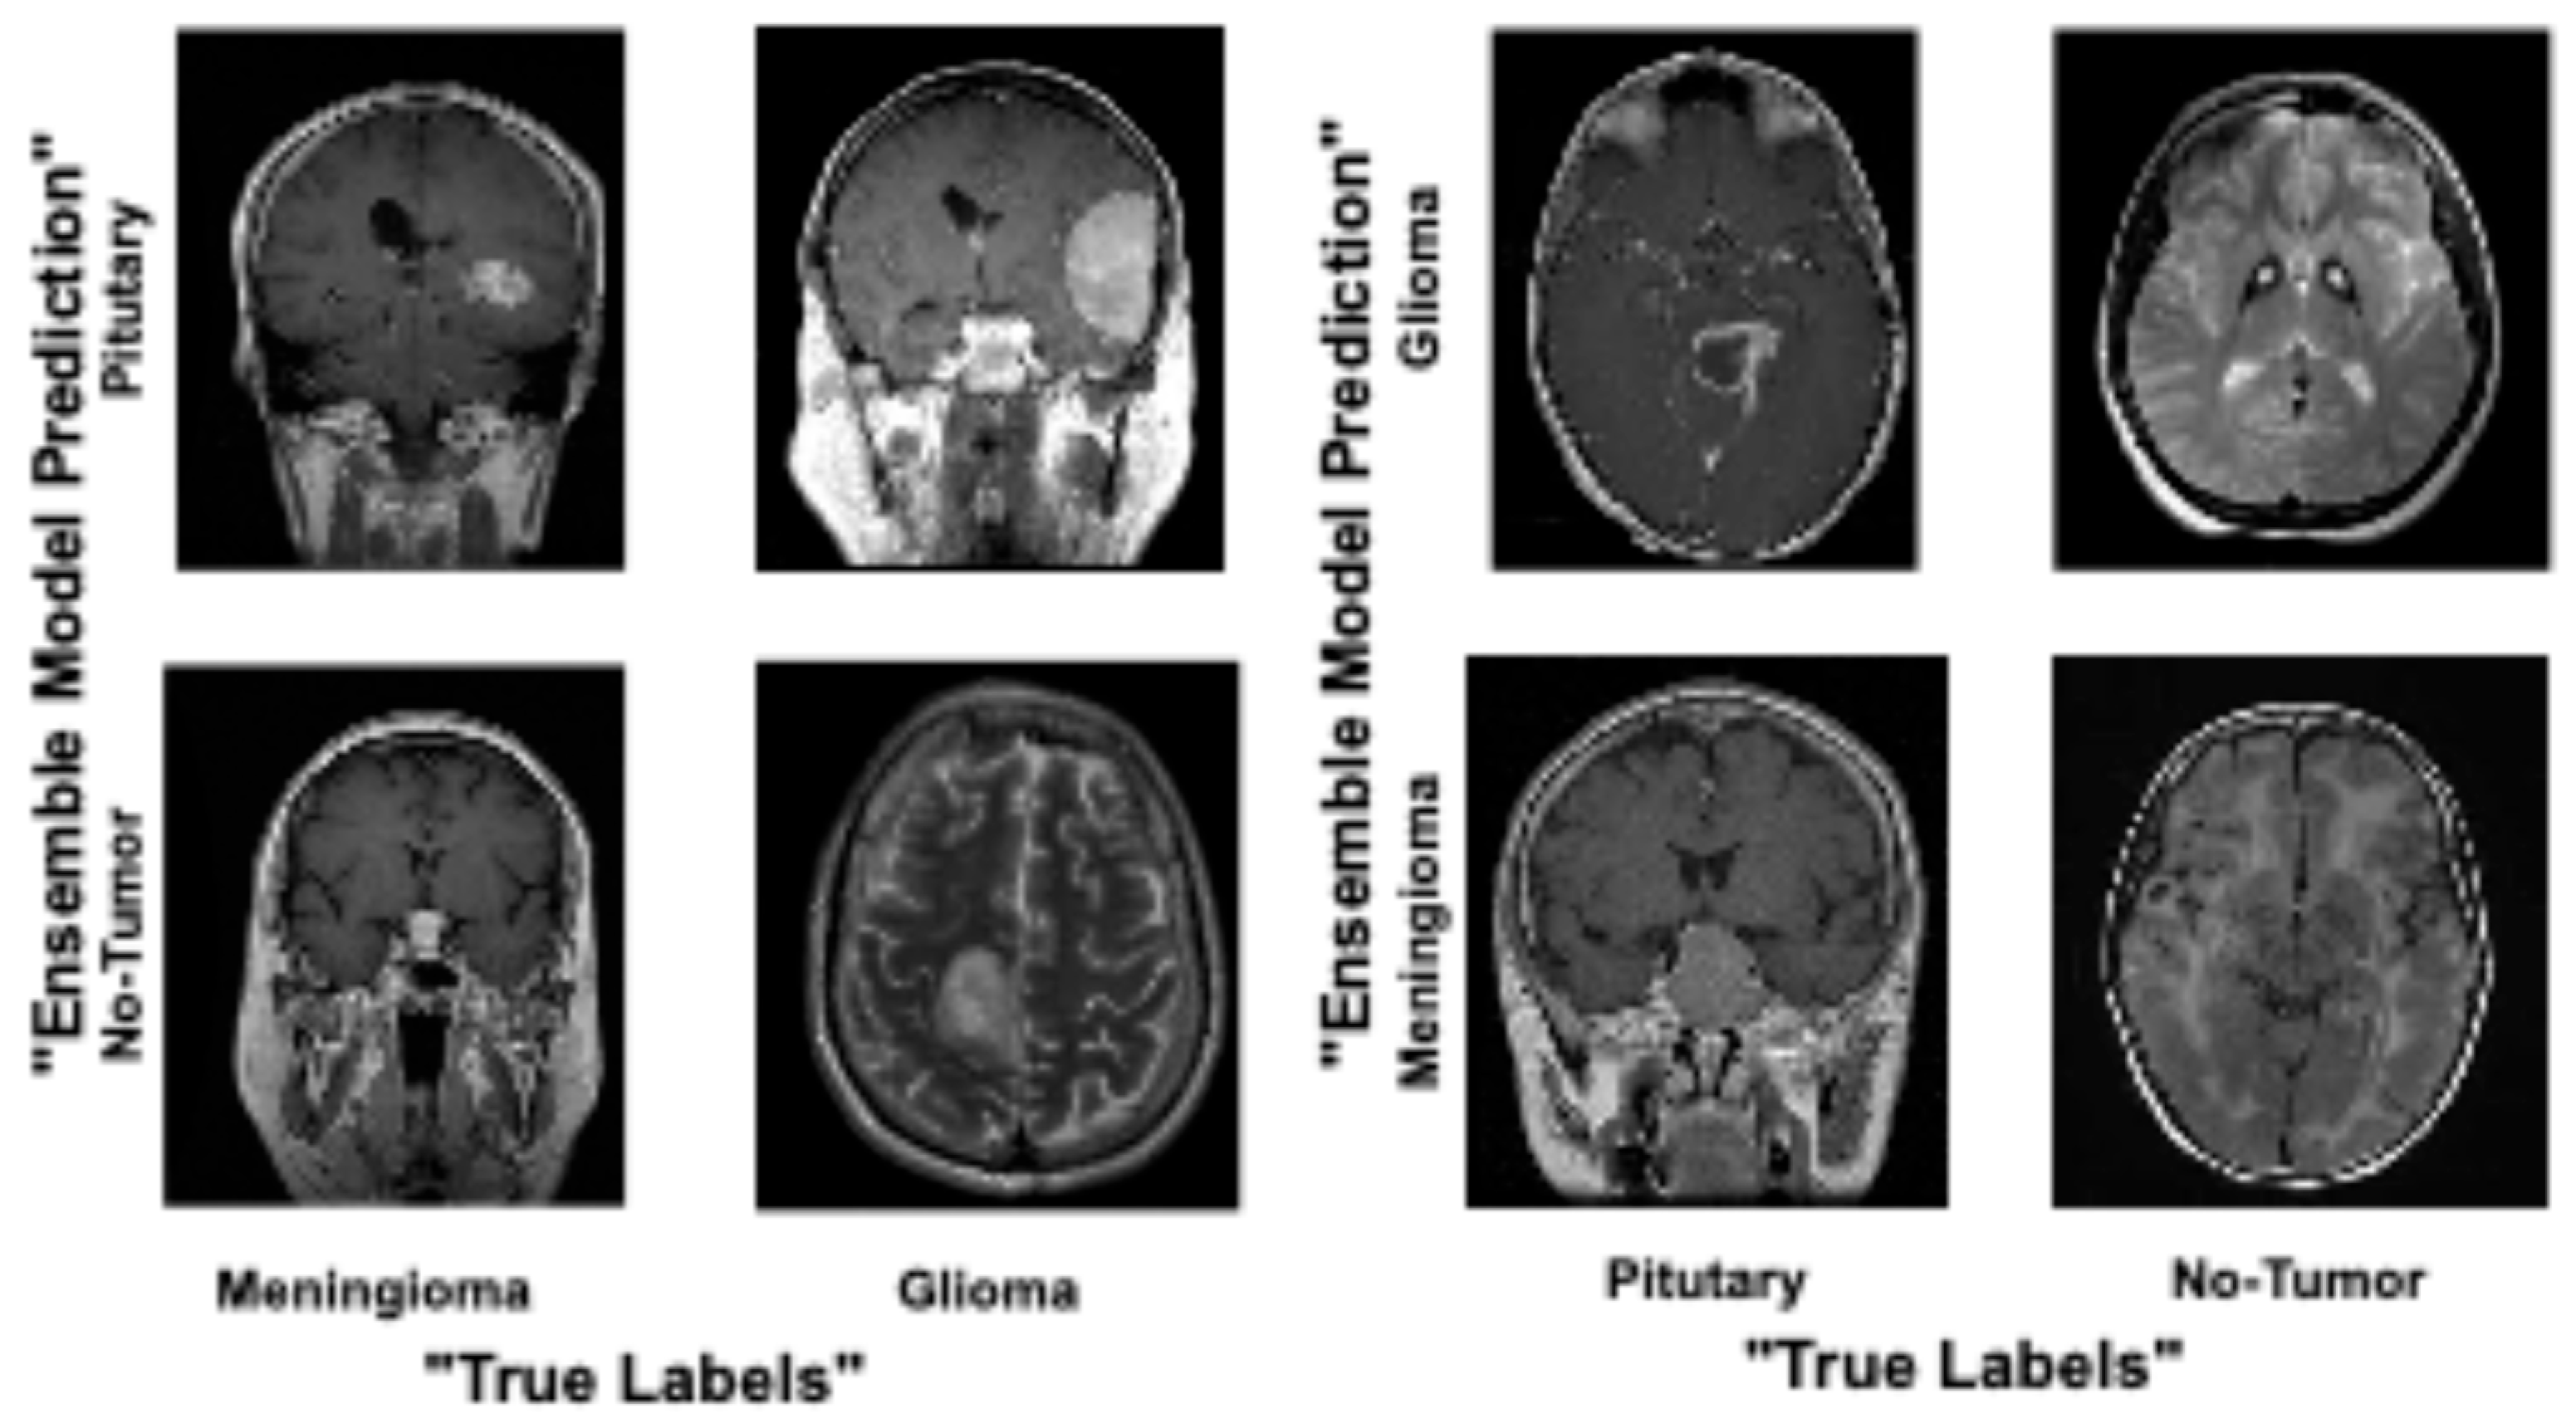

4. Results and Analysis